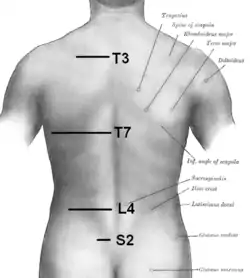

Muscles connecting the upper extremity to the vertebral column. Left iliac crest is labeled in red.

Muscles connecting the upper extremity to the vertebral column. Left iliac crest is labeled in red. Plan of ossification of the hip bone